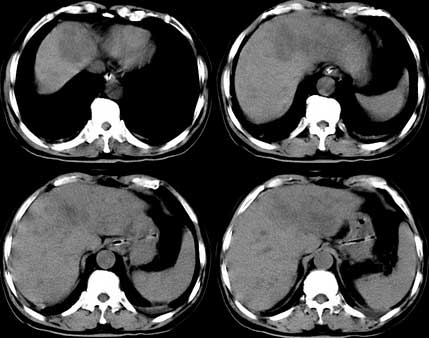

患者 男性 65岁,2005年8月行胆管癌切除术(切除胰头 胆囊及十二指肠),今行ct复查,请会诊,有没有复发?(近期患者发烧,重度黄疸)

是单纯复发还是复发伴肝内转移?我个人认为应当再考虑一下,并倾向于后者。肝总管下端内、后侧见不规则软组织块影,部分侵入肝总管内。其边缘凸凹不平且模糊不清,渐进性不均匀强化。肝总管于此处管径突然变小,其上肝总管显著扩张,内见较均匀液性密度,管壁也很光整。肝内多发低密度病灶用复发引起的肝内胆管扩张显然不能解释的通,病灶分布与胆内胆管的走行不一致。而且随着时间的延续病变更加清晰,没有强化,部分还可见牛眼征。

考虑胆囊癌术后复发及肝转移,肝门区胆管扩张明显,左肾囊肿。

术后复发及肝转移,左肾囊肿。